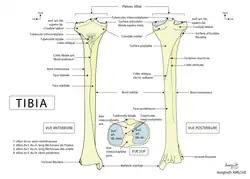

Le tibia est un os long constitué d'une épiphyse proximale, d'une diaphyse et d'une épiphyse distale.

Épiphyse proximale

L'épiphyse proximale est volumineuse, allongée transversalement et légèrement déjetée en arrière.

Sa face supérieure horizontale constitue le plateau tibial. Il est constitué de deux tubérosités formant les condyles du tibia : un latéral et un médial. Les deux sont recouverts de cartilage hyalin qui constituent les surfaces articulaires supérieures du tibia (la surface articulaire du condyle médial du tibia et la surface articulaire supérieure du condyle latéral du tibia). Elles sont séparées par la surface intercondylaire.

Diaphyse ou corps du tibia

Le bord antérieur Le corps du tibia est la portion du tibia situé entre la partie inférieure des condyles et au-dessus de la partie articulée avec le talus.

Il est prismatique de section triangulaire. Il est le plus large à ses extrémités, la partie la plus étroite se situant entre son tiers inférieur et ses deux tiers supérieurs.

Il présente trois bords (antérieur, interosseux et médial) et de trois faces (médiale, latérale et postérieure).

Face médiale

Face latérale

Face postérieure

Bord antérieur

Bord interosseux

Bord médial

Épiphyse distale

L'épiphyse distale du tibia est moins volumineuse que l'épiphyse proximale. Elle est plus large dans le sens transversal que dans le sens antéro-postérieur.

Elle présente cinq faces : antérieure, postérieure, latérale, médiale et inférieure.